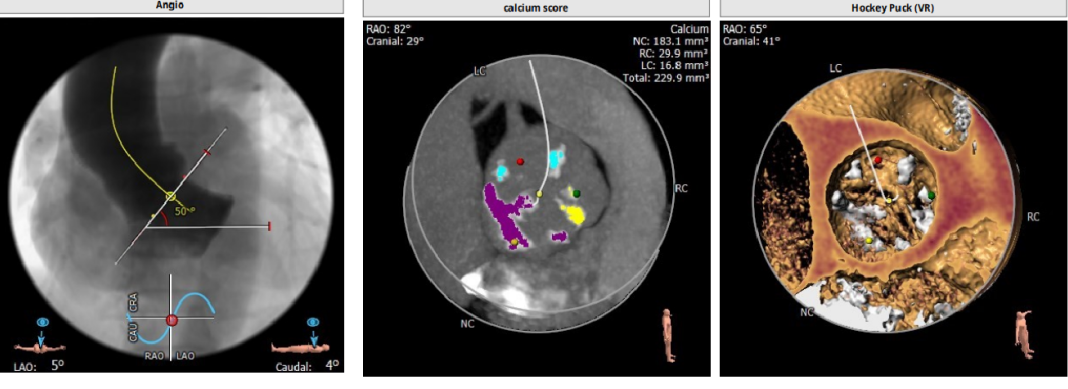

type1型二叶瓣,重度钙化

钙化主要分布在右冠窦和无冠窦

左冠高度稍低,存在一定冠脉风险

Annulus:25.8mm

LVOT:27.1mm

STJ 30.6mm

升主动脉:38.4mm

LM:10mm

RM:12.2mm

CT分析

以3个窦消失最低点确认的平面作为虚拟瓣环平面初步筛选瓣膜尺寸。自展瓣参考周长得出的Annulus直径,该病人为25.8,根据自膨胀瓣膜特点需要oversize,初步判断为29/32瓣膜。LVOT直径大于Annulus,短径24mm,足够限制瓣膜,提供锚定支撑力。STJ高度足够,可提供足够空间给原有瓣叶,过宽的STJ则无法提供释放中锚定支撑力。

窦部的空间与左右冠脉开口高度结合瓣叶形态,是否增厚可以初步判断瓣叶是否会在瓣膜植入后遮挡冠脉开口造成急性的冠脉堵塞。该病人左冠开口略低,且钙化集中在右冠和无冠窦,判断冠脉风险较高。需术中球扩判断是否进行冠脉保护。

升主动脉未见增宽,心脏角度合适极重度钙化,多集中在基底部位二叶瓣重度钙化THV需要downsize选择26/29瓣膜。

钙化积分:

0-400 轻度

400-600 中度

600-800 重度

800以上 极重度钙化

投照角度:左冠切线位球囊扩张时采用,可以观察左冠是否有冠脉风险,工作体位三窦平均拉开,无冠窦位于最低处方便瓣膜释放和定位心室大。